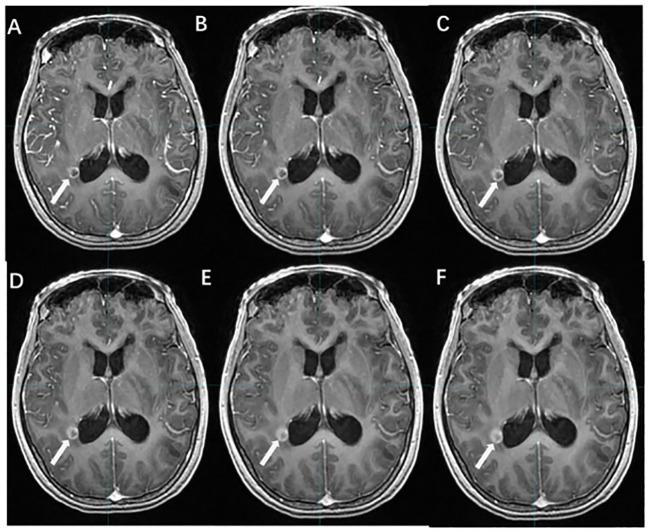

Brain metastases (BMs) are the most prevalent intracranial malignant tumors in adults and are the leading cause of mortality attributed to malignant brain diseases. Radiotherapy (RT) plays a critical role in the treatment of BMs, with local RT techniques such as stereotactic radiosurgery (SRS)/stereotactic body radiotherapy (SBRT) showing remarkable therapeutic effectiveness. The precise determination of gross tumor target volume (GTV) is crucial for ensuring the effectiveness of SRS/SBRT. Multimodal imaging techniques such as CT, MRI, and PET are extensively used for the diagnosis of BMs and GTV determination. With the development of functional imaging and artificial intelligence (AI) technology, there are more innovative ways to determine GTV for BMs, which significantly improve the accuracy and efficiency of the determination. This article provides an overview of the progress in GTV determination for RT in BMs.